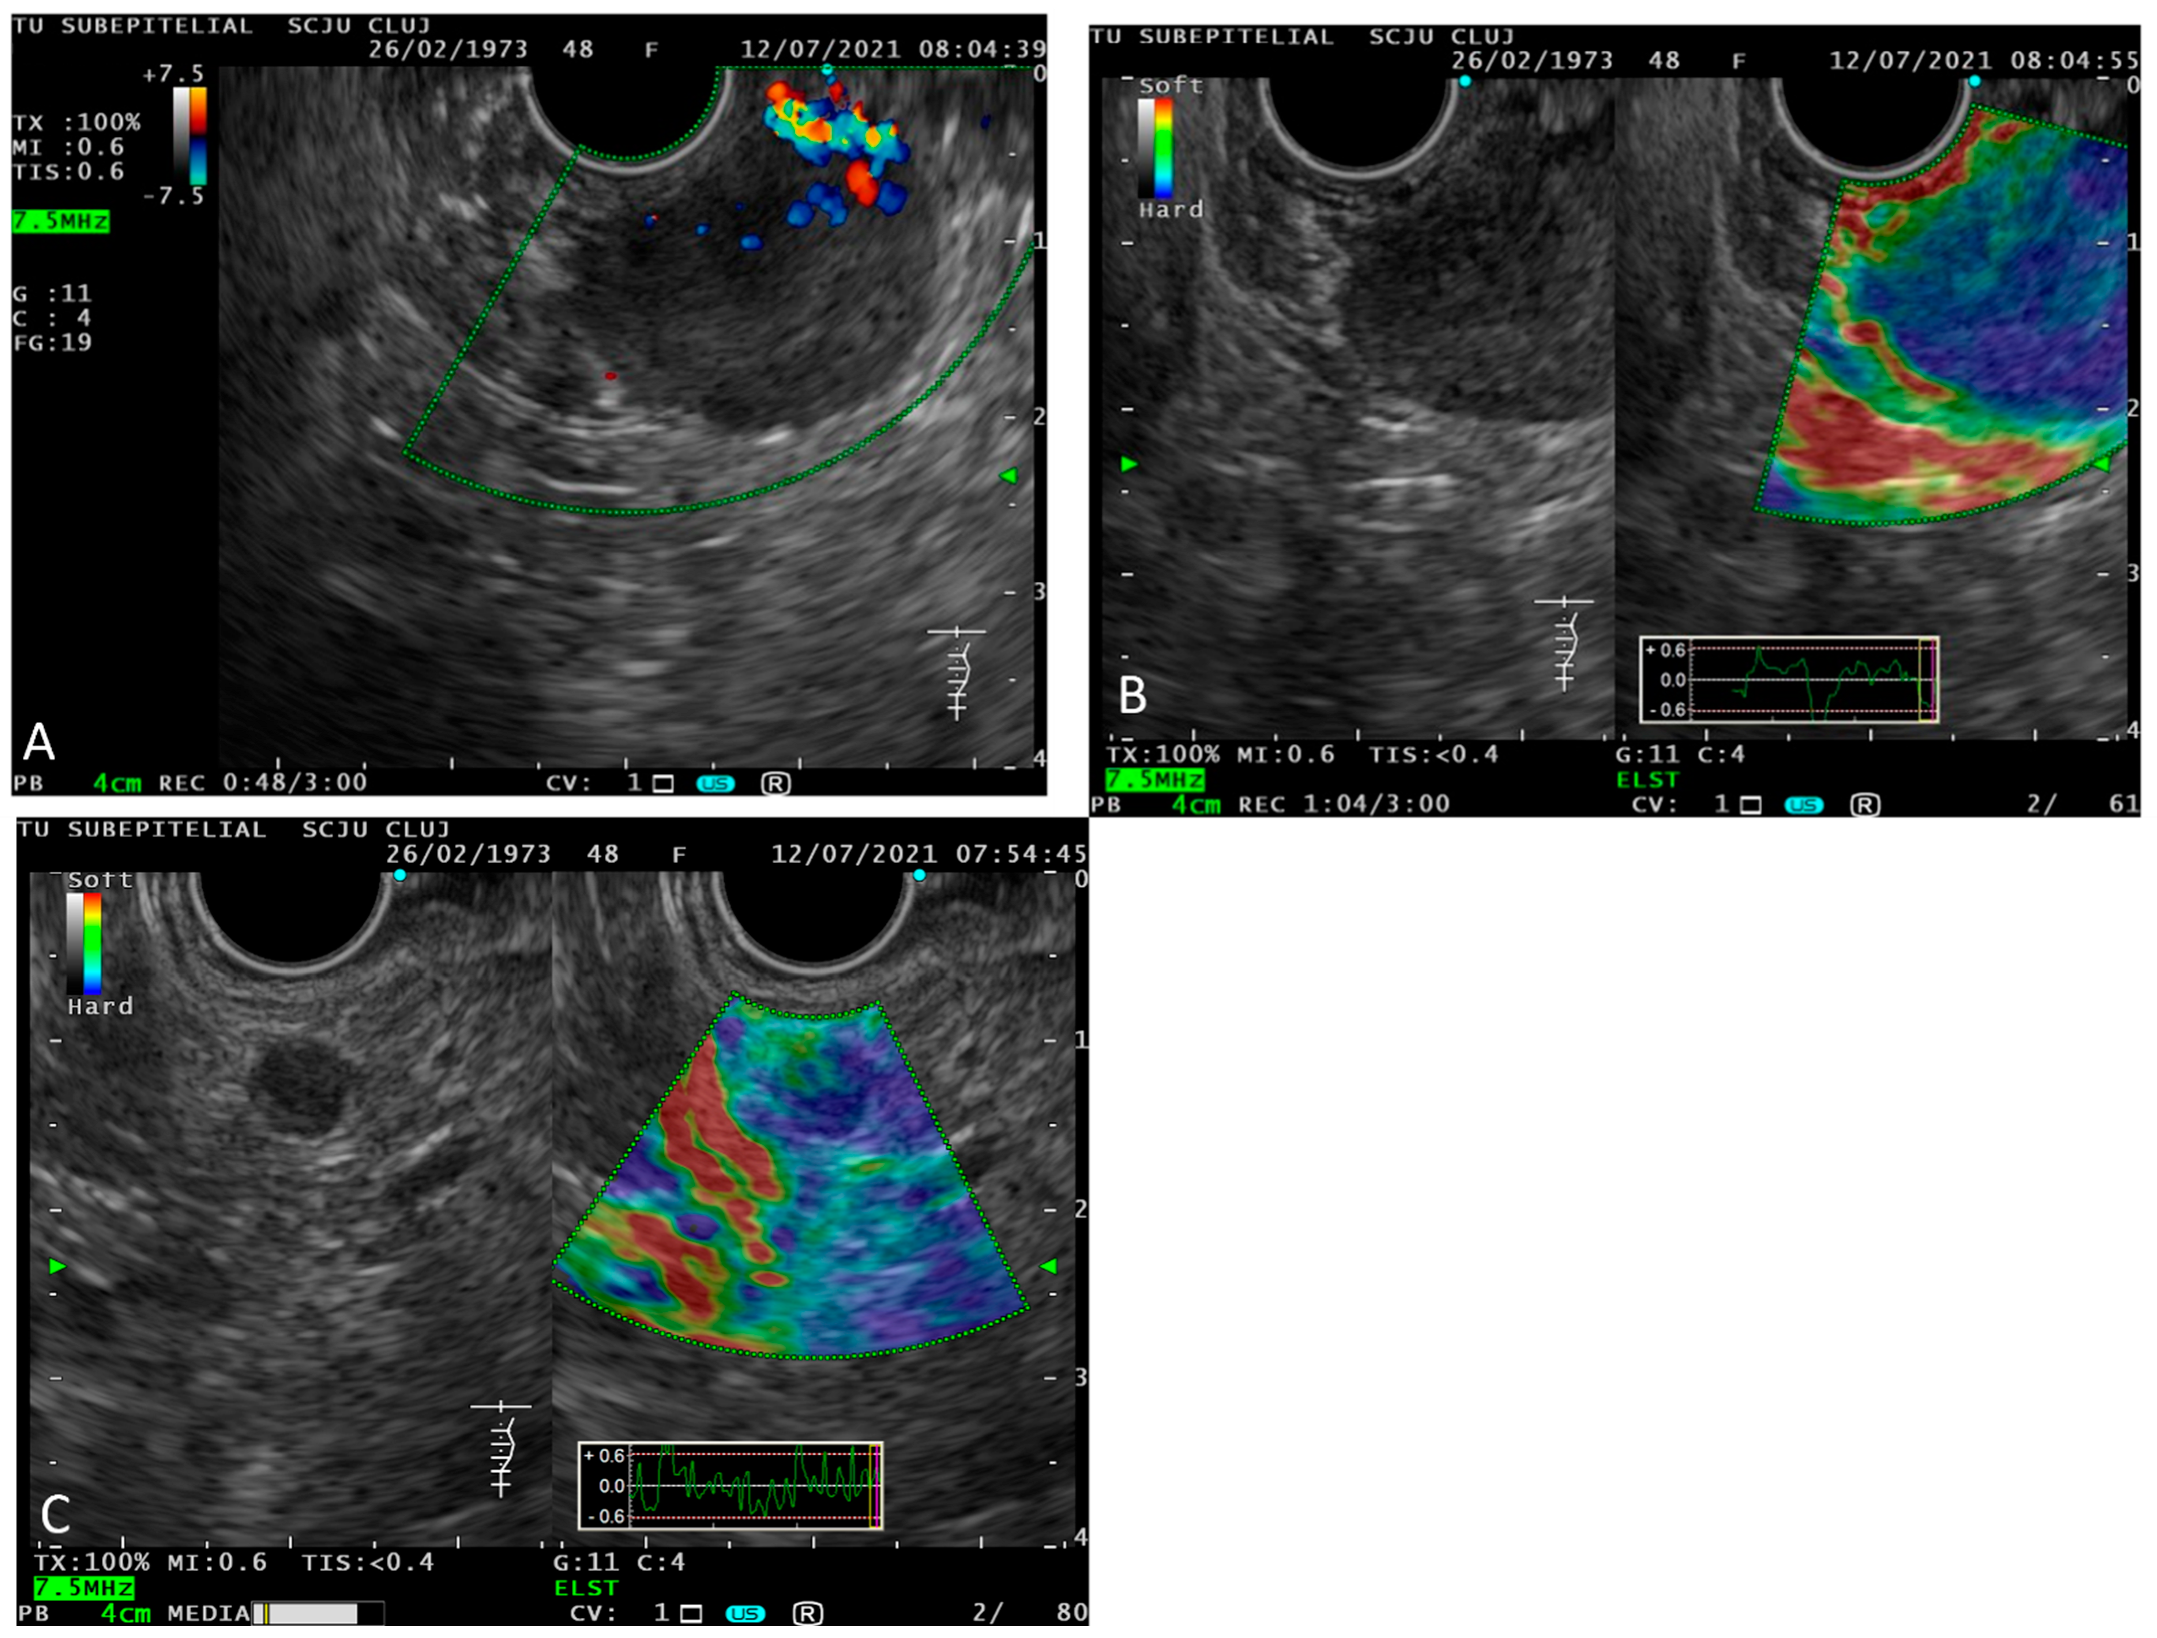

2.3. Endoscopic Ultrasound (EUS)